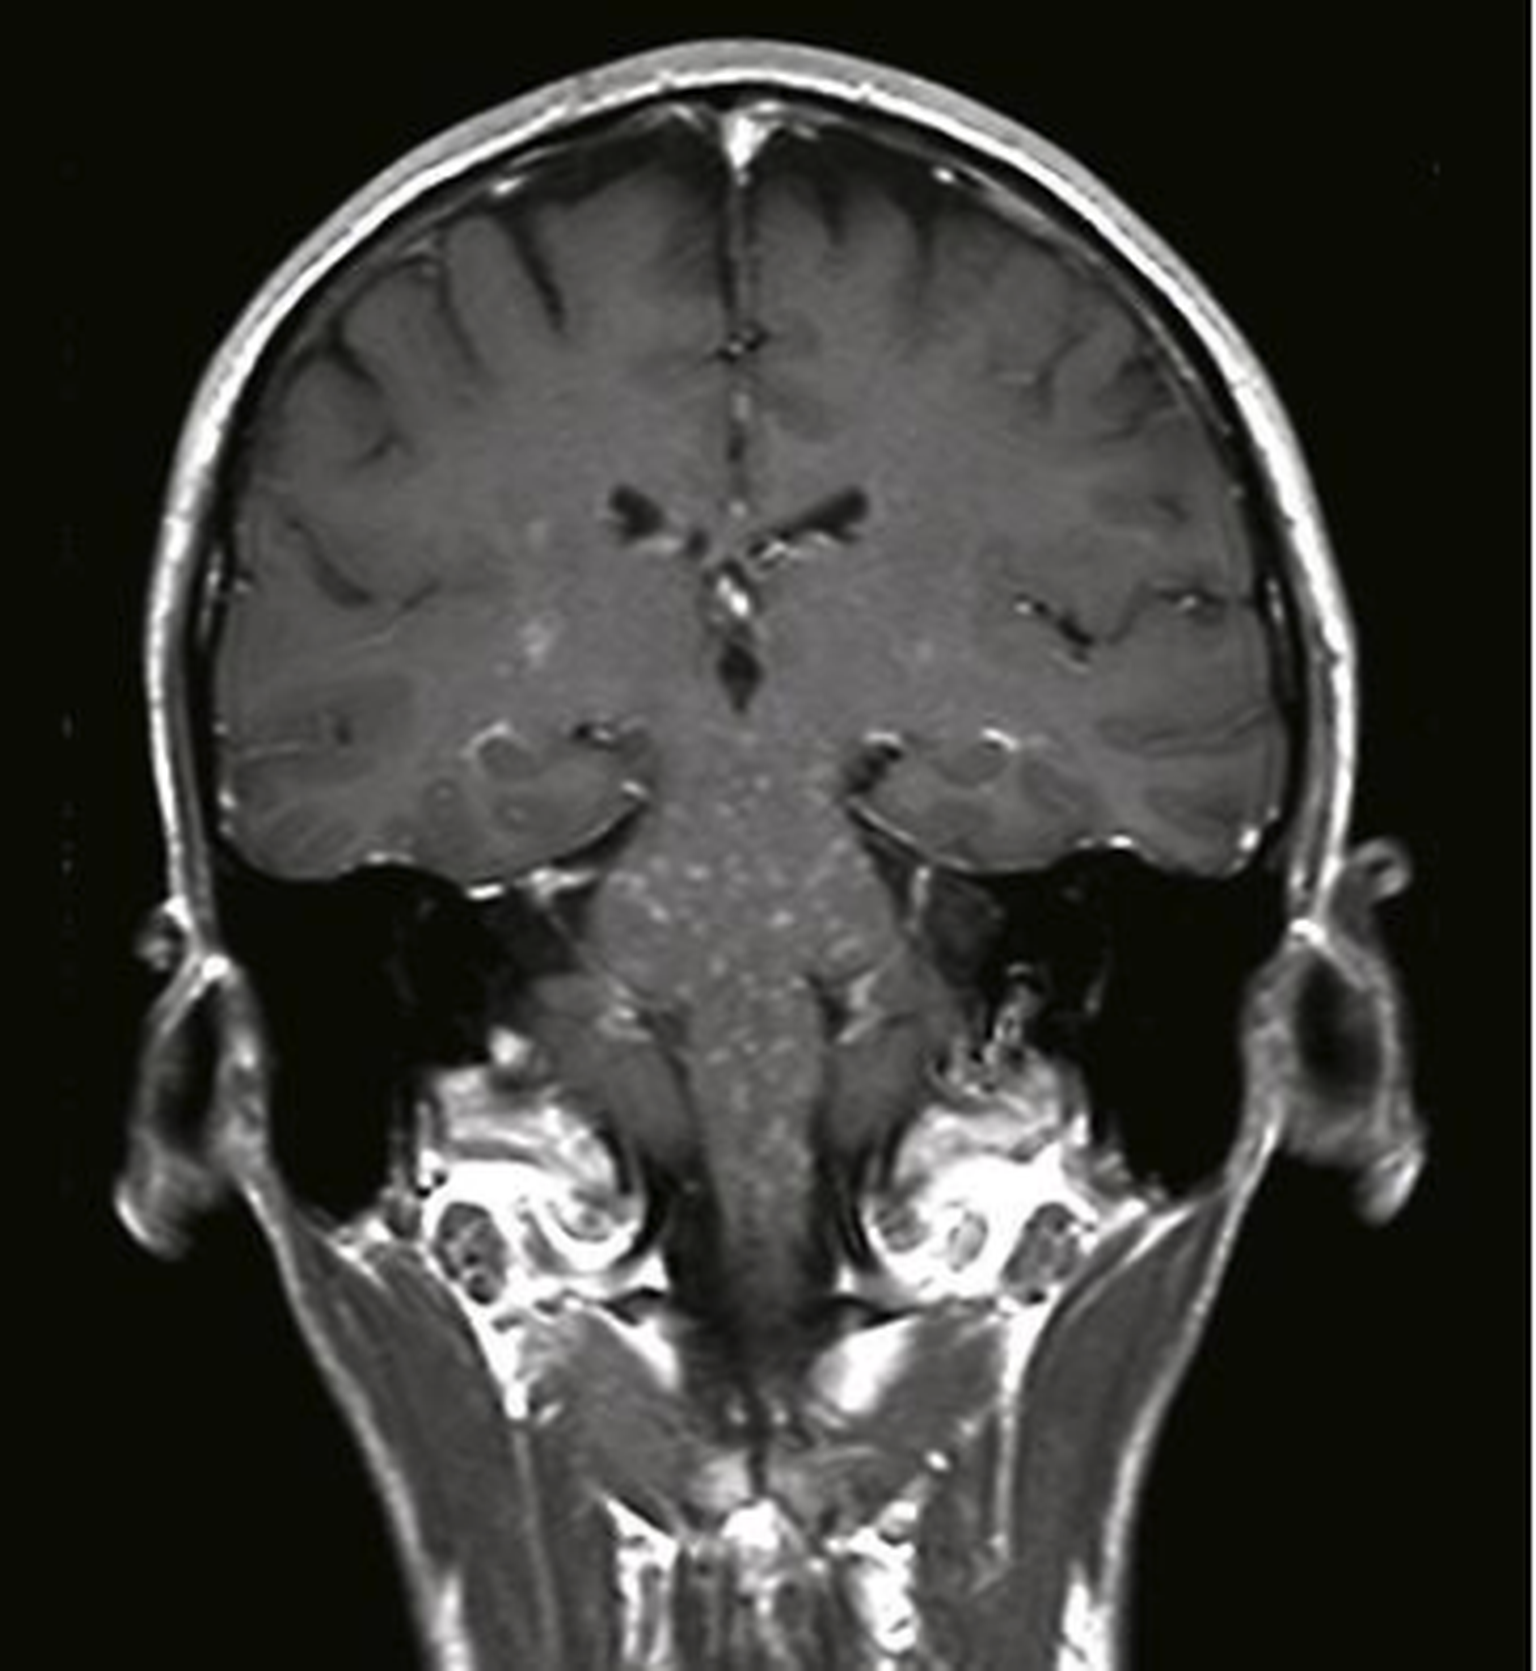

Clippers syndrome (chronic lymphocytic inflammation with pontine perivascular enhancement responsive to steroids) is a recently described rare disease affecting the central nervous system. The paper describes clippers syndrome in a patient who has been followed up in a clinic for 10 years. Frosch m., kautz g., reers b. The article provides a detailed review of the literature resources. Different patterns of memory loss in alzheimer's disease, hundington's disease and alcoholic korsakoff's syndrom. The modern views on etiology, pathogenesis of clippers syndrome, the clinical signs. Principles and practice of medical genetics, london, 1983. Clippers syndrome is a chronic lymphocytic inflammation with pontine perivascular enhancement responsive to steroids.

Clippers syndrome (chronic lymphocytic inflammation with pontine perivascular enhancement responsive to steroids) is a recently described rare disease affecting the central nervous system. Spannende, sehr gut gemachte tv dokumentation über eine seltene krankheit: Clippers syndrome is a chronic lymphocytic inflammation with pontine perivascular enhancement responsive to steroids. Frosch m., kautz g., reers b. Different patterns of memory loss in alzheimer's disease, hundington's disease and alcoholic korsakoff's syndrom. The article provides a detailed review of the literature resources. The modern views on etiology, pathogenesis of clippers syndrome, the clinical signs. Clippers syndrome (chronic lymphocytic inflammation with pontine perivascular enhancement responsive to steroids) is a recently described rare disease affecting the central nervous the paper describes clippers syndrome in a patient who has been followed up in a clinic for 10 years. Natolochnaya, olga & cherkasov, aleksandr. Principles and practice of medical genetics, london, 1983. Panic attack as the syndrom of the xxi century. European journal of psychological studies. Autoimmune stem encephalitis syndrome clippers.